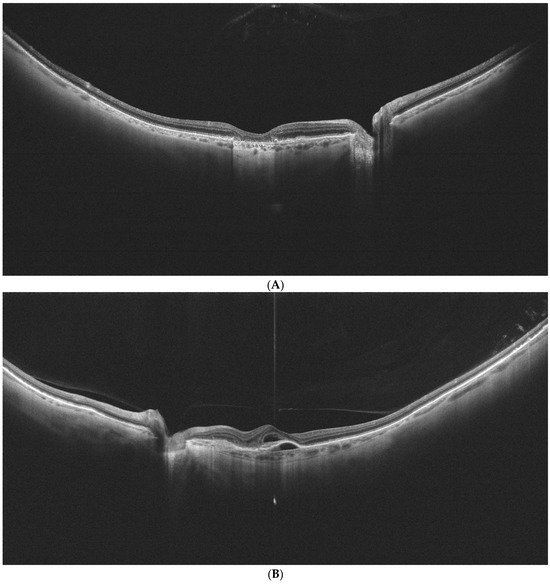

Figure 2A–C show examples of UWF-OCT images of AMD and healthy patients.

Figure 2.

(A) is an example of UWF-OCT in geographic atrophy. Increased penetration of the retina is noted in the central part of the posterior pole. The choroid is distinctly thin. Retinal thickness values state 284 µm, 312 µm, and 227 µm respectively for the central, perifoveal, and peripheral zones. For the choroid, these thicknesses constitute 184 µm, 174 µm, and 152.75 µm, respectively. (B) Exudative form of AMD in UWF-OCT scan. Subretinal and sub-RPE fluid is observed in the retinal center. As in the previous scan, the choroid appears thin. Retinal thicknesses are observed at 345 µm in the central zone, 266.81 µm for the perifoveal, and 206 µm for the peripheral. Choroidal thickness values stand for 223 µm, 168.25 µm, and 139.25 µm, respectively, for the analyzed sectors. (C) UWF-OCT scan in a healthy individual. The choroid is apparently thicker compared to patients with AMD from (A,B). Retinal thickness measurements are noted at 351 µm, 299 µm, and 216.5 µm for central, perifoveal. and peripheral zones, respectively. Choroidal thickness values for these zones are, respectively, 398 µm, 328.87 µm, and 252.37 µm.